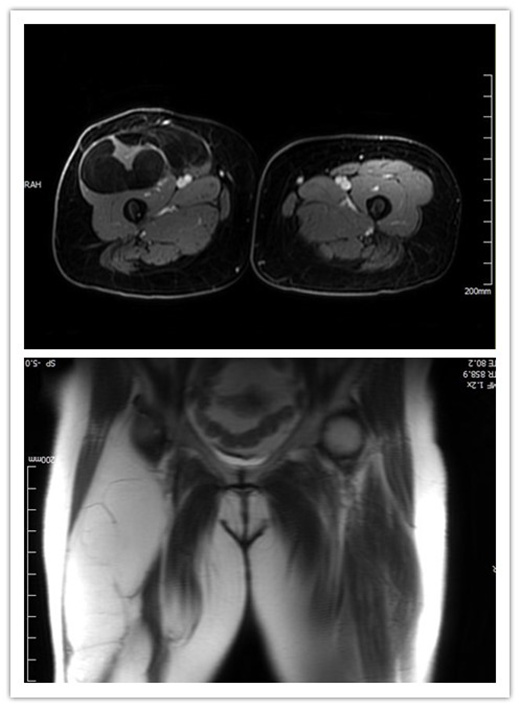

此次入院,烧伤整形与创面修复外科诊断考虑患者脂肪肉瘤复发,其右侧腹股沟上方5cm至膝上5cm,肿物位于阔筋膜深面,质软,活动度尚可,体积大,无触痛及压痛。入院后,患者完善右下肢核磁提示为右大腿前方大小13cm×30cm×5.6cm,上缘达股骨头水平,下至股骨下段,考虑脂肪肉瘤复发。

如此巨大脂肪肉瘤,在临床中实属罕见,术中可见脂肪肉瘤位于阔筋膜深面,范围上至腹股沟上方5cm,下至膝上5cm,包裹股直肌,血供丰富,术中离断股直肌,彻底切除肿瘤及其包裹的股直肌,手术顺利,出血量少,效果满意。